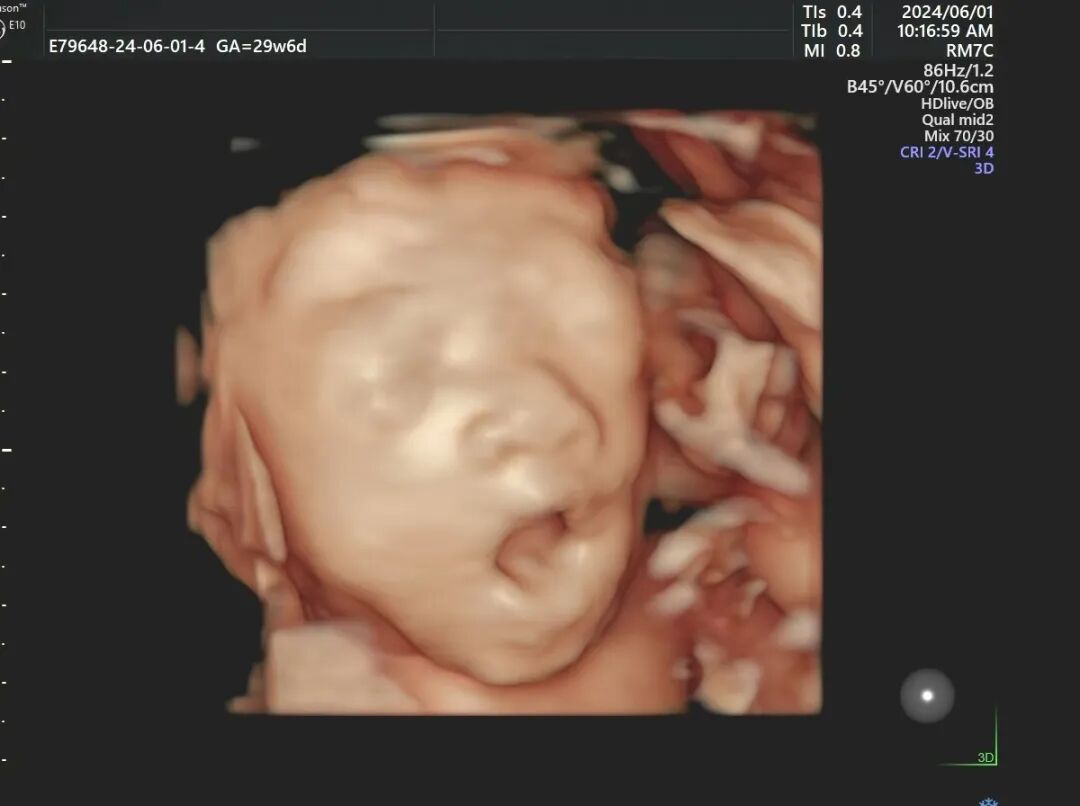

(我院E10四维彩超实拍)

打哈欠、吐舌头

除了兴奋的时候会对妈妈拳打脚踢,宝宝其他时间都在睡大觉,快睡着的时候十分可爱。一会吐吐舌头,一会打哈欠,还有各种表情搞怪,整个一表情包。